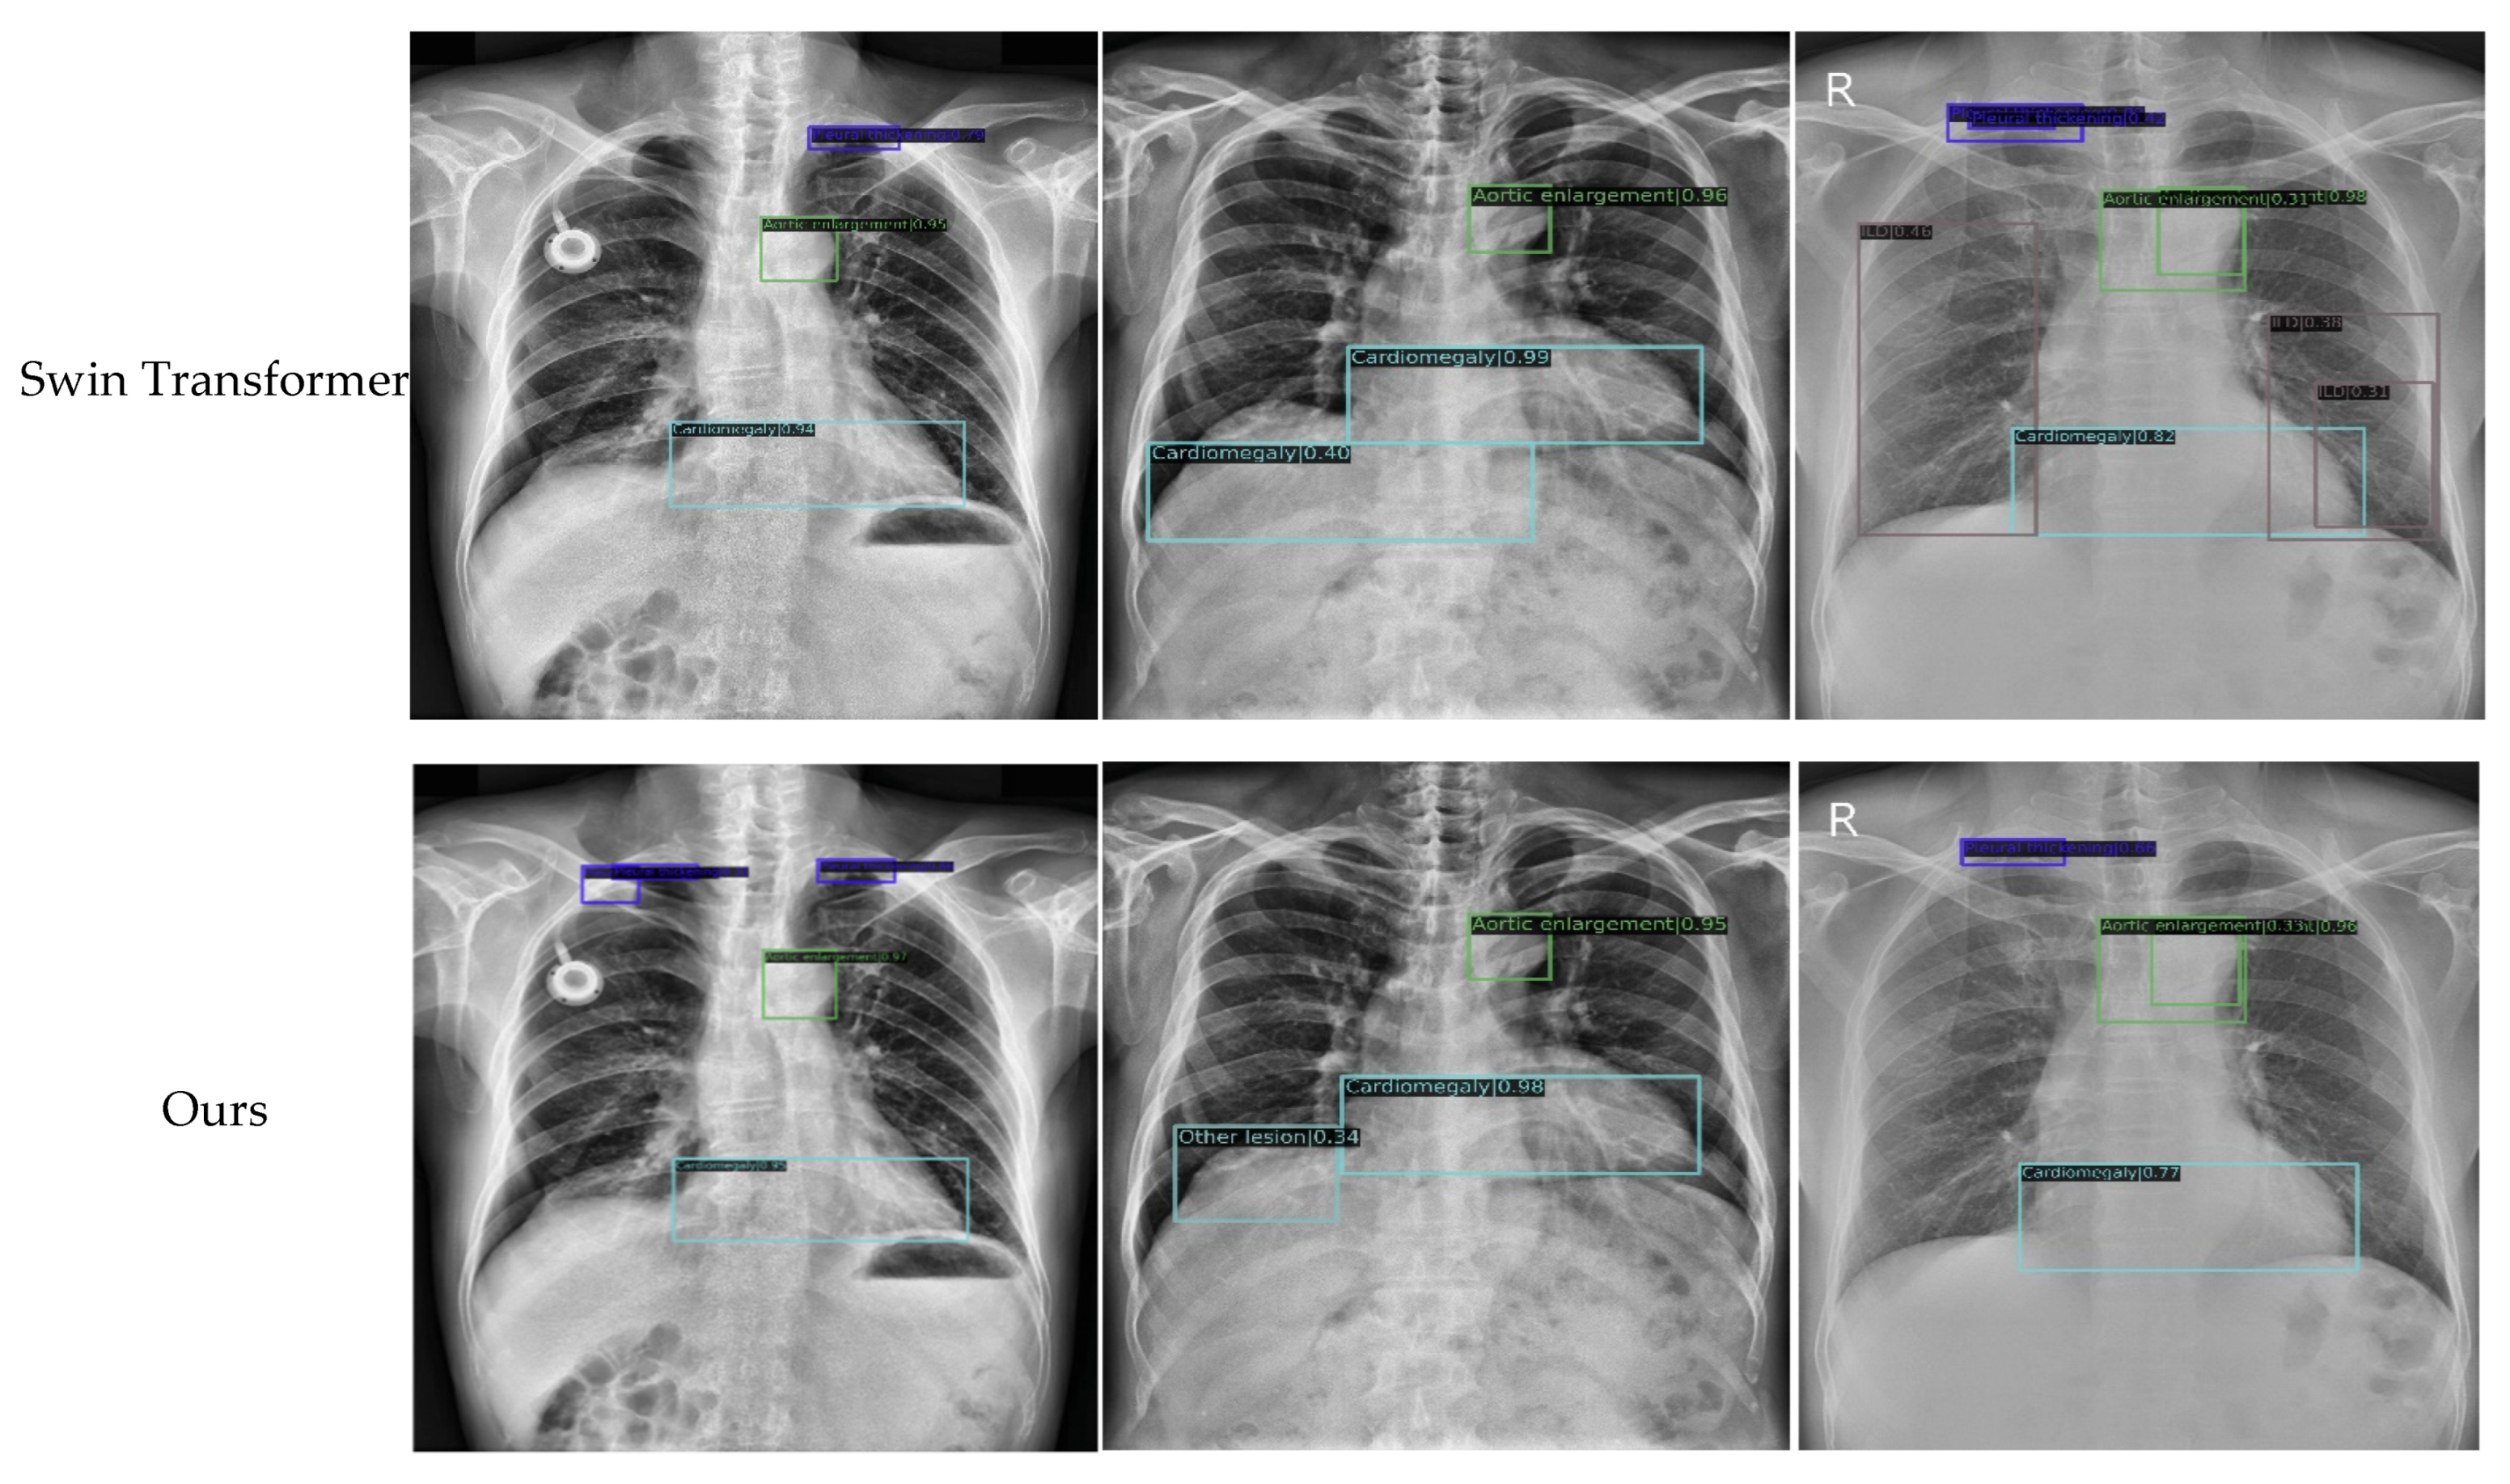

For an objective evaluation of our approach, three popular approaches (i.e., cascade R-CNN [43], TridentNet [44], and Libra R-CNN [45]) and two of the latest approaches (Sparse R-CNN [46] and Swin Transformer [18]) were selected for comparison, all of which achieved the state of the art in object detection while publishing. For the experimental parameters of the compared methods, we used the best configuration recommended by the mm-detection toolbox. Specifically, for cascade R-CNN, TridentNet, and Libra R-CNN, the initial learning rate, momentum, and weight decay were set to 0.02, 0.9, and 0.0001, respectively, and the SGD optimizer was employed to regulate the learning rate; for Sparse R-CNN and Swin Transformer, the initial learning rate and weight decay were set to 0.000025 and 0.0001, respectively, and the AdamW optimizer was employed. For the sake of a fair comparison, the proposed method used the same parameters with cascade R-CNN, TridentNet, and Libra R-CNN, since the parameters they required were similar. In addition, in terms of the convergence criteria, the batch size and training period were set to 2 and 12, respectively, for all compared methods. The AP and mAP of the compared methods in the VinDr-CXR dataset are listed in Table 2, where the values marked in bold indicated the best performance. The P–R diagrams of some representative abnormal categories for the compared methods are shown in Figure 7. To demonstrate the effectiveness of the proposed approach more intuitively, detection examples of the compared methods are shown in Figure 8.

Figure 8.

Detection examples of the compared methods.

The following findings were obtained from the above experimental results.

First, the proposed method achieved the highest mAP of 0.362, which was 3.2% higher than that of cascade R-CNN (baseline) and 4.8%, 5.6%, 11.3%, and 2.6% higher than that of TridentNet, Libra R-CNN, Sparse R-CNN, and Swin Transformer, respectively. Second, different models were suitable for different types of chest anomaly detection, but our model achieved the highest AP in most categories; that is, we achieved the best performance in five out of the fourteen categories. For example, Libra R-CNN achieved a superior detection precision in pleural effusion, whereas Sparse R-CNN was suitable for detecting large-scale chest abnormalities such as aortic enlargement. Another recently published method that has to be mentioned is Swin Transformer, which showed good potential in the anomaly detection of chest X-rays and achieved the highest AP in three categories, i.e., calcification, pneumo-thorax, and pulmonary fibrosis. However, the proposed method achieved the best results in most categories, including large-scale and small-scale abnormalities, such as infiltration, atelectasis, pleural thickening, consolidation, and cardiomegaly.

Second, by observing the anomaly detection examples shown in Figure 8, visual comparisons also proved that the proposed method generally achieved more accurate detection results, and that our approach could effectively identify the specific locations of various types of chest anomalies. Even for small targets, our method exhibited a high degree of coincidence with the ground truth. This was mainly due to the fact that we improved the backbone networks with embedded local features and context information. Moreover, with the optimized feature fusion process, information from different scales was rationally used to obtain a more accurate prediction region.

Finally, to carry out an interpretative analysis of our model, we used Grad-CAM [13] to generate a heat map visualization. Some representative examples of our model and the baseline are presented in Figure 10. By analyzing the results, the following conclusions could be drawn. First, compared with the baseline, the heat map generated by our model was more consistent with the ground truth. Second, the results of our qualitative prediction box also showed a certain correspondence with the heat map. This implied that Grad-CAM had a certain faithfulness to our model, and that the proposed method had good reliability. In general, the heat map produced with our method highlighted the discriminative regions that were more consistent with the visual judgment of radiologists, although it must be noted that this method of comparison was a relatively subjective way of evaluating the proposed method.

Figure 10.

The heat map visualization for proposed model and baseline.